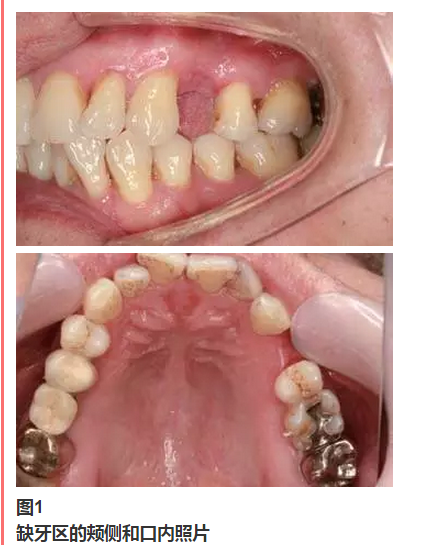

從圖1可以看出患者缺牙區(qū)的間隙充足,牙齦健康,頰側(cè)軟組織略有凹陷。

永久修復(fù)后3年進(jìn)行回訪,種植體骨結(jié)合穩(wěn)定,美學(xué)效果良好。